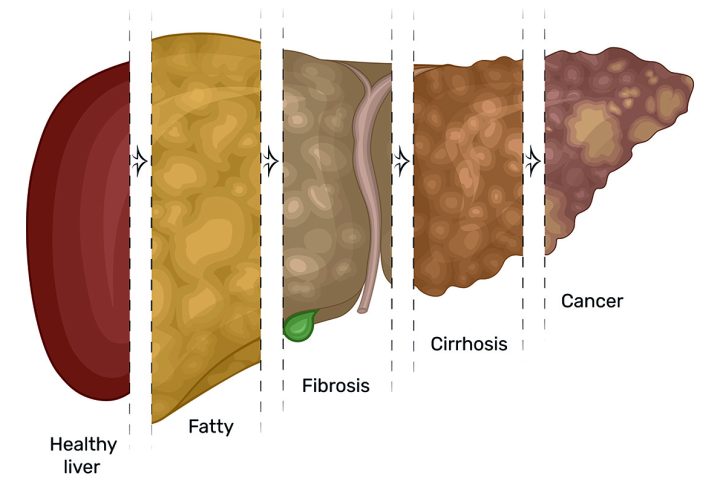

این بیماری به ۴ گرید از نظر میزان پیشرفت دستهبندی میشود:

گرید ۱:

گرید 1 کبد چرب سادهترین نوع آن است که دلیل آن خوردن مواد غذایی ناسالم است. البته این گرید با افزایش فعالیتهای روزانه و تغذیه سالم کاملاً برطرف میگردد.

گرید ۲:

گرید 2 کبد چرب در این حالت وضعیت بیمار کمی سختتر و پیچیدهتر میشود این حالت از کبد چرب، رژیم غذایی خاص خود را نیز دارد.

گرید ۳:

گرید 3 کبد چرب تنها با بهبود سبک زندگی قابل درمان خواهد بود ورزش، تغذیه مناسب (کاهش مصرف انواع گوشت، فست فودها، چربیها و غذاهای چرب و…) مدیریت استرس و دیگر موارد. البته این هشداری است برای افراد دارای کبد چرب گرید ۲ و ۱ که در درمان بیماری خود سهل انگاری میکنند.

گرید ۴:

گرید 4 کبد چرب که به سیروز کبدی معروف است، در صورت اقدام نکردن برای بهبود بیماری پیوند کبد برای فرد احتیاج میشود.

سیروز کبدی چیست؟

تجمع بیش از حد چربی در کبد میتواند باعث التهاب این اندام شود. التهاب، باعث آسیب به کبد و ایجاد زخم یا اسکار میشود که به عنوان فیبروز کبدی نیز شناخته میشود. فیبروز شدید کبدی، سیروز نامیده میشود که در موارد شدید، میتواند منجر به نارسایی کبد شود.